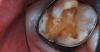

A 9-year-old boy had a partially erupted mandibular first molar with much hypocalcification of the occlusal surface and a large caries lesion involving the occlusal and buccal surfaces (Figure 1). The patient complained of continuing sensitivity to cold stimulus and air inspiration. Because the tooth was only partially erupted, consideration for stainless steel crown full coverage had to be delayed. As an interim repair, it was decided to debride the carious tooth substance and place a light-hardened calcium silicate/mineral trioxide aggregate (MTA) liner, followed by a bonded restoration. After inferior alveolar block anesthetic injection and cotton roll isolation, cavity outline form was cut using a high-speed, water-cooled, medium-grit cylindrical diamond bur (Figure 2). Insufficient eruption precluded use of a rubber dam. A large, round bur at slow speed was used to debride the carious enamel and dentin. The prepared surfaces were swabbed for two 60-second applications of a 5% glutaraldehyde/HEMA solution for desensitization and disinfection of the preparation.6,7 Cavity liner was then injected and spread over the deepest sections of the cavity floor and hardened with the visible light beam (Figure 3). After a self-etching bonding agent was applied over the remaining enamel surfaces, without the need for any type of matrix, an RMGI bioactive ionic resin-based composite was injected, in one portion, into the preparation and spread over the four cusps using a ball burnisher. This restorative complex was then photo-polymerized using two 20-second exposures of the visible light beam (1,200 mW/cm2). The restoration was trimmed and finished with large, round diamond burs at slow speed, and occlusion was evaluated with articulating paper and adjusted.

A 9-year-old presented with hypoplasia, hypocalcification, and caries.

Figure 1

The tooth was prepared for interim sedative restoration.

Figure 2

Cavity liner was placed and light-hardened.

Figure 3